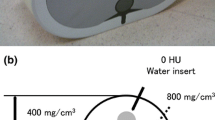

To analyze the image quality of the coronary arteries objectively, four parameters, the image noise, CT density, SNR, and contrast-to-noise ratio (CNR), were analyzed for each data set by a single reader [11, 12].

Image noise was measured as the standard deviation of CT attenuation measured at the air space outside of the anterior thoracic wall. Subsequently, SNR was calculated by dividing the attenuation of the left main by the image noise. As for CNR, the CT attenuation of the epicardial fat surrounding the artery was measured by placing a region of interest immediately next to the artery and was subtracted from that of the left main coronary artery to find the contrast, which was then divided by the image noise, resulting in the CNR. The four parameters were obtained in the same manner for all images of both groups.